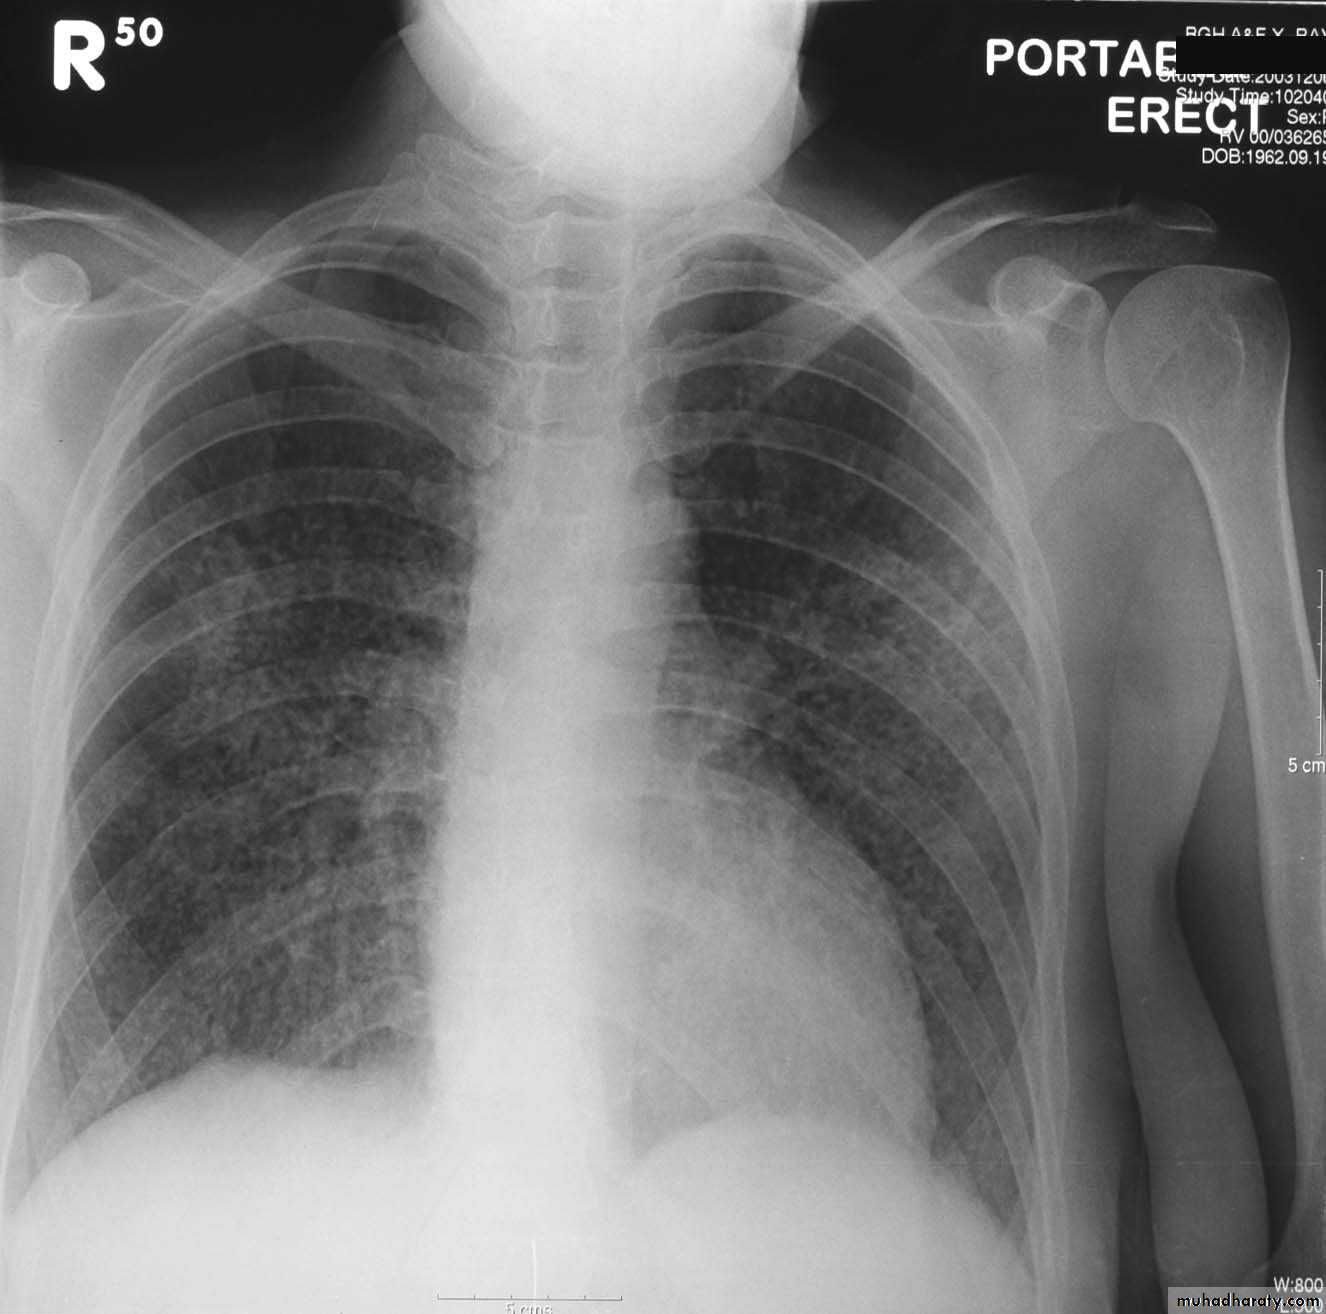

Pleural Effusion on Chest Radiographs.

Posteroanterior (A) and lateral (B) chest radiographs demonstrate the typical meniscoid appearance (arrows) in a patient with a left pleural effusion

Hydropneumothorax.

When fluid and air are present in the pleural space on an upright chest x-ray, a perfectly straight horizontal line will extend all the way from the spine to the edge of the pleural cavity. In this patient, a loculated right basilar hydropneumothorax is present.

The air/fluid interface is easily seen (arrows). If this were a lung abscess, the air/fluid level would be very unlikely to extend all the way from the medial to the lateral aspect of the hemithorax.

Subpulmonary pleural effusion. On the (A) erect PA and (B) lateral radiograph the effusion simulates a high hemidiaphragm. (C) Ultrasound and (D) CT clearly show that the effusion is located above the diaphragm. Arrows = diaphragmatic area.